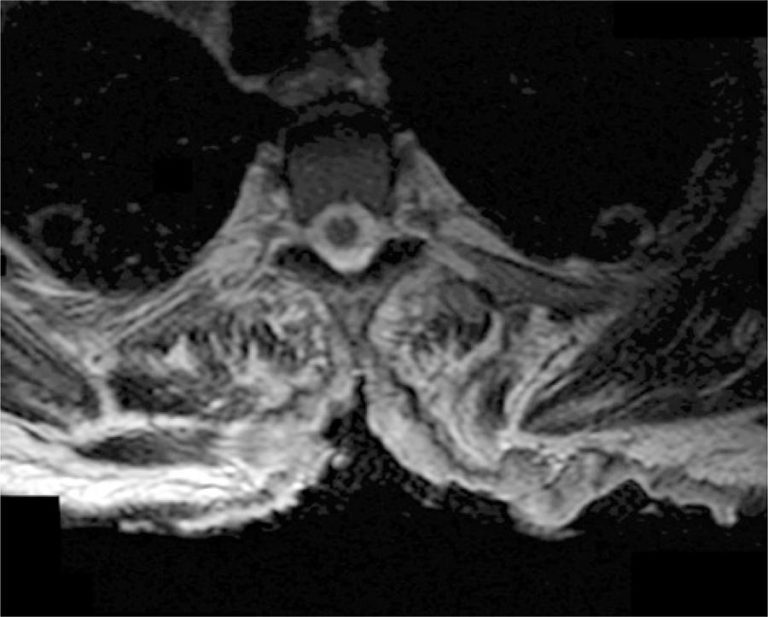

Não havia histórico de malignidade, condições imunossupressoras, exposição a doença contagiosa, ou relato de viagem para fora dos Estados Unidos. Os sinais vitais estavam dentro dos padrões normais. O exame físico revelou lesão ulcerativa medindo 26cmx16cm, abrangendo os corpos vertebrais de T1 a T8, com exposição dos processos espinhosos e musculatura paravertebral mais proeminente no nível de T5. A lesão continha áreas de sangramento pontilhados, tecido granulado e drenagem copiosa de seroma. As margens estavam bem definidas e sem lesões satélites (). Além da palidez da pele no restante do exame físico, que incluiu avaliação neurológica completa, não foram observados outros fatores significantes. Na emergência, realizou-se tomografia computadorizada do tórax/abdômen, pélvis, além de duas biópsias individuais por punção do leito da úlcera. A tomografia computadorizada mostrou erosão dos processos espinhosos torácicos, porém não havia evidência de doença metastática. O hemograma relevou hemoglobina e leucócitos de 4,6g/dL e 6,9 células x 10/µL, respectivamente. Na internação, o paciente recebeu transfusão devido à sua anemia assintomática e iniciou terapia com sulfato ferroso.